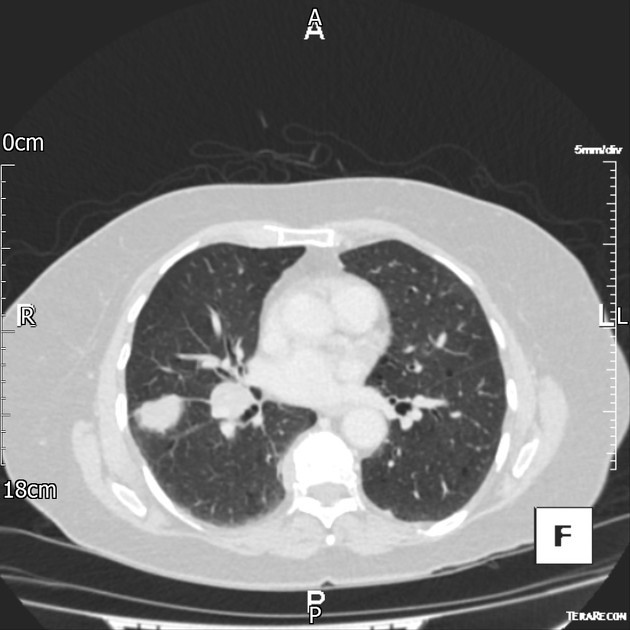

PACIENTE 35 ANOS, SEXO MASCULINO, DISPNÉIA HÁ 4 DIAS.

opacidades em vidro fosco difusas associadas a espessamento de septos interlobulares (crazy paving)

PROTEINOSE ALVEOLAR